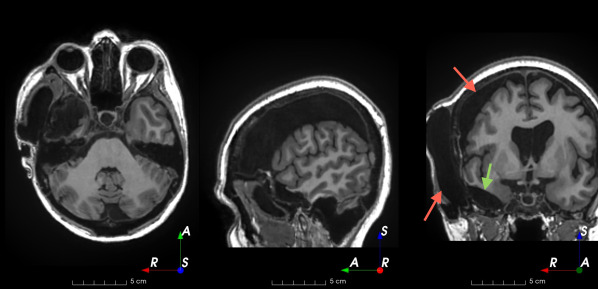

Refer to caption

(a)

(b)

(c)

(d)

(e)

(f)

Figure 3: Manual labels from Rater A (green) and Rater D, the model trained with PubFull + EpiPre + Pseudo (magenta). Errors caused by a (a) small resection, (b) blood clot in cavity and (c) brain shift; segmentations corresponding to the (d) 50th, (e) 75th and (f) 100th percentiles giving a DSC of 81.7, 86.5 and 93.8, respectively.